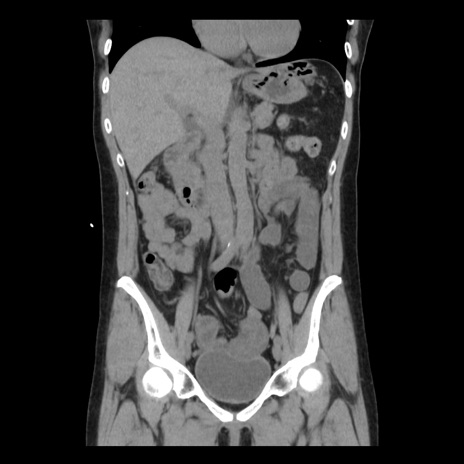

症例10(冠状断像)

【症例】 50歳代女性

【主訴】 腹痛

【現病歴】前日生レバーを食べた。今朝に排便あり。 昼前に突然発症の腹痛を生じ、当院救急外来を受診した。

【既往歴】 子宮筋腫にてで子宮全摘後

【身体所見】 意識清明、腹部:平坦、軟、下腹部やや左を中心に圧痛・反跳痛あり、筋性防御あり

【データ】WBC 7800、CRP 0.07